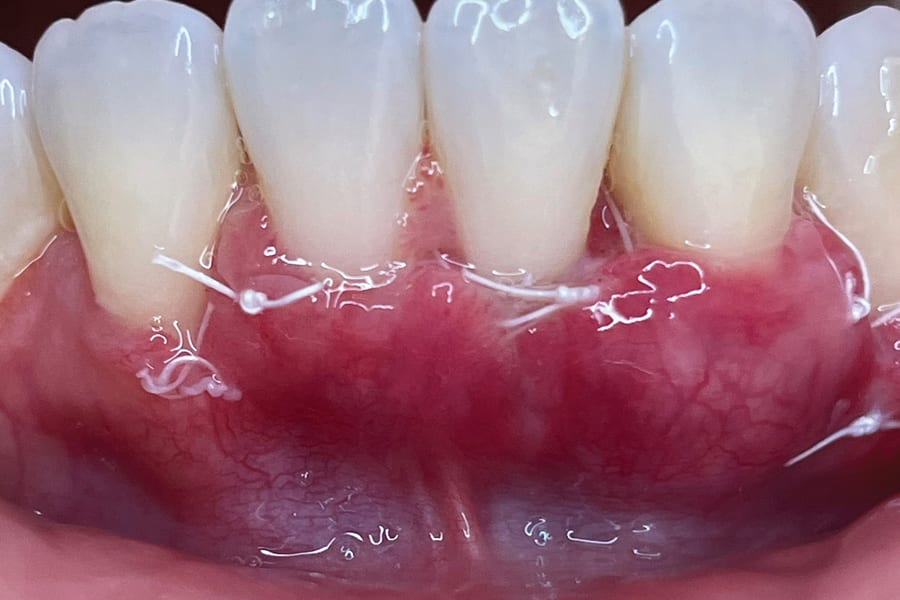

Although spontaneous improvement of the investing tissues is often observed through orthodontic correction (Figure 7 and Figure 13),5 additional corrective action is frequently indicated afterwards, particularly when cosmetics are to be considered. A recession defect case is depicted in Figure 17 through Figure 26 in which corrective action was necessary and accomplished through aligner therapy followed by connective tissue grafting.6 It should be noted that although this corrective scheme may successfully achieve an acceptable cosmetic and functional result, it is not likely a regenerative outcome in the sense that a previously dehisced root surface typically will not attain ligamentous insertion into freshly laid cementum. A long junctional epithelium or connective tissue attachment at best is the more likely outcome. Consequently, a preventive approach initially would be more desirable.